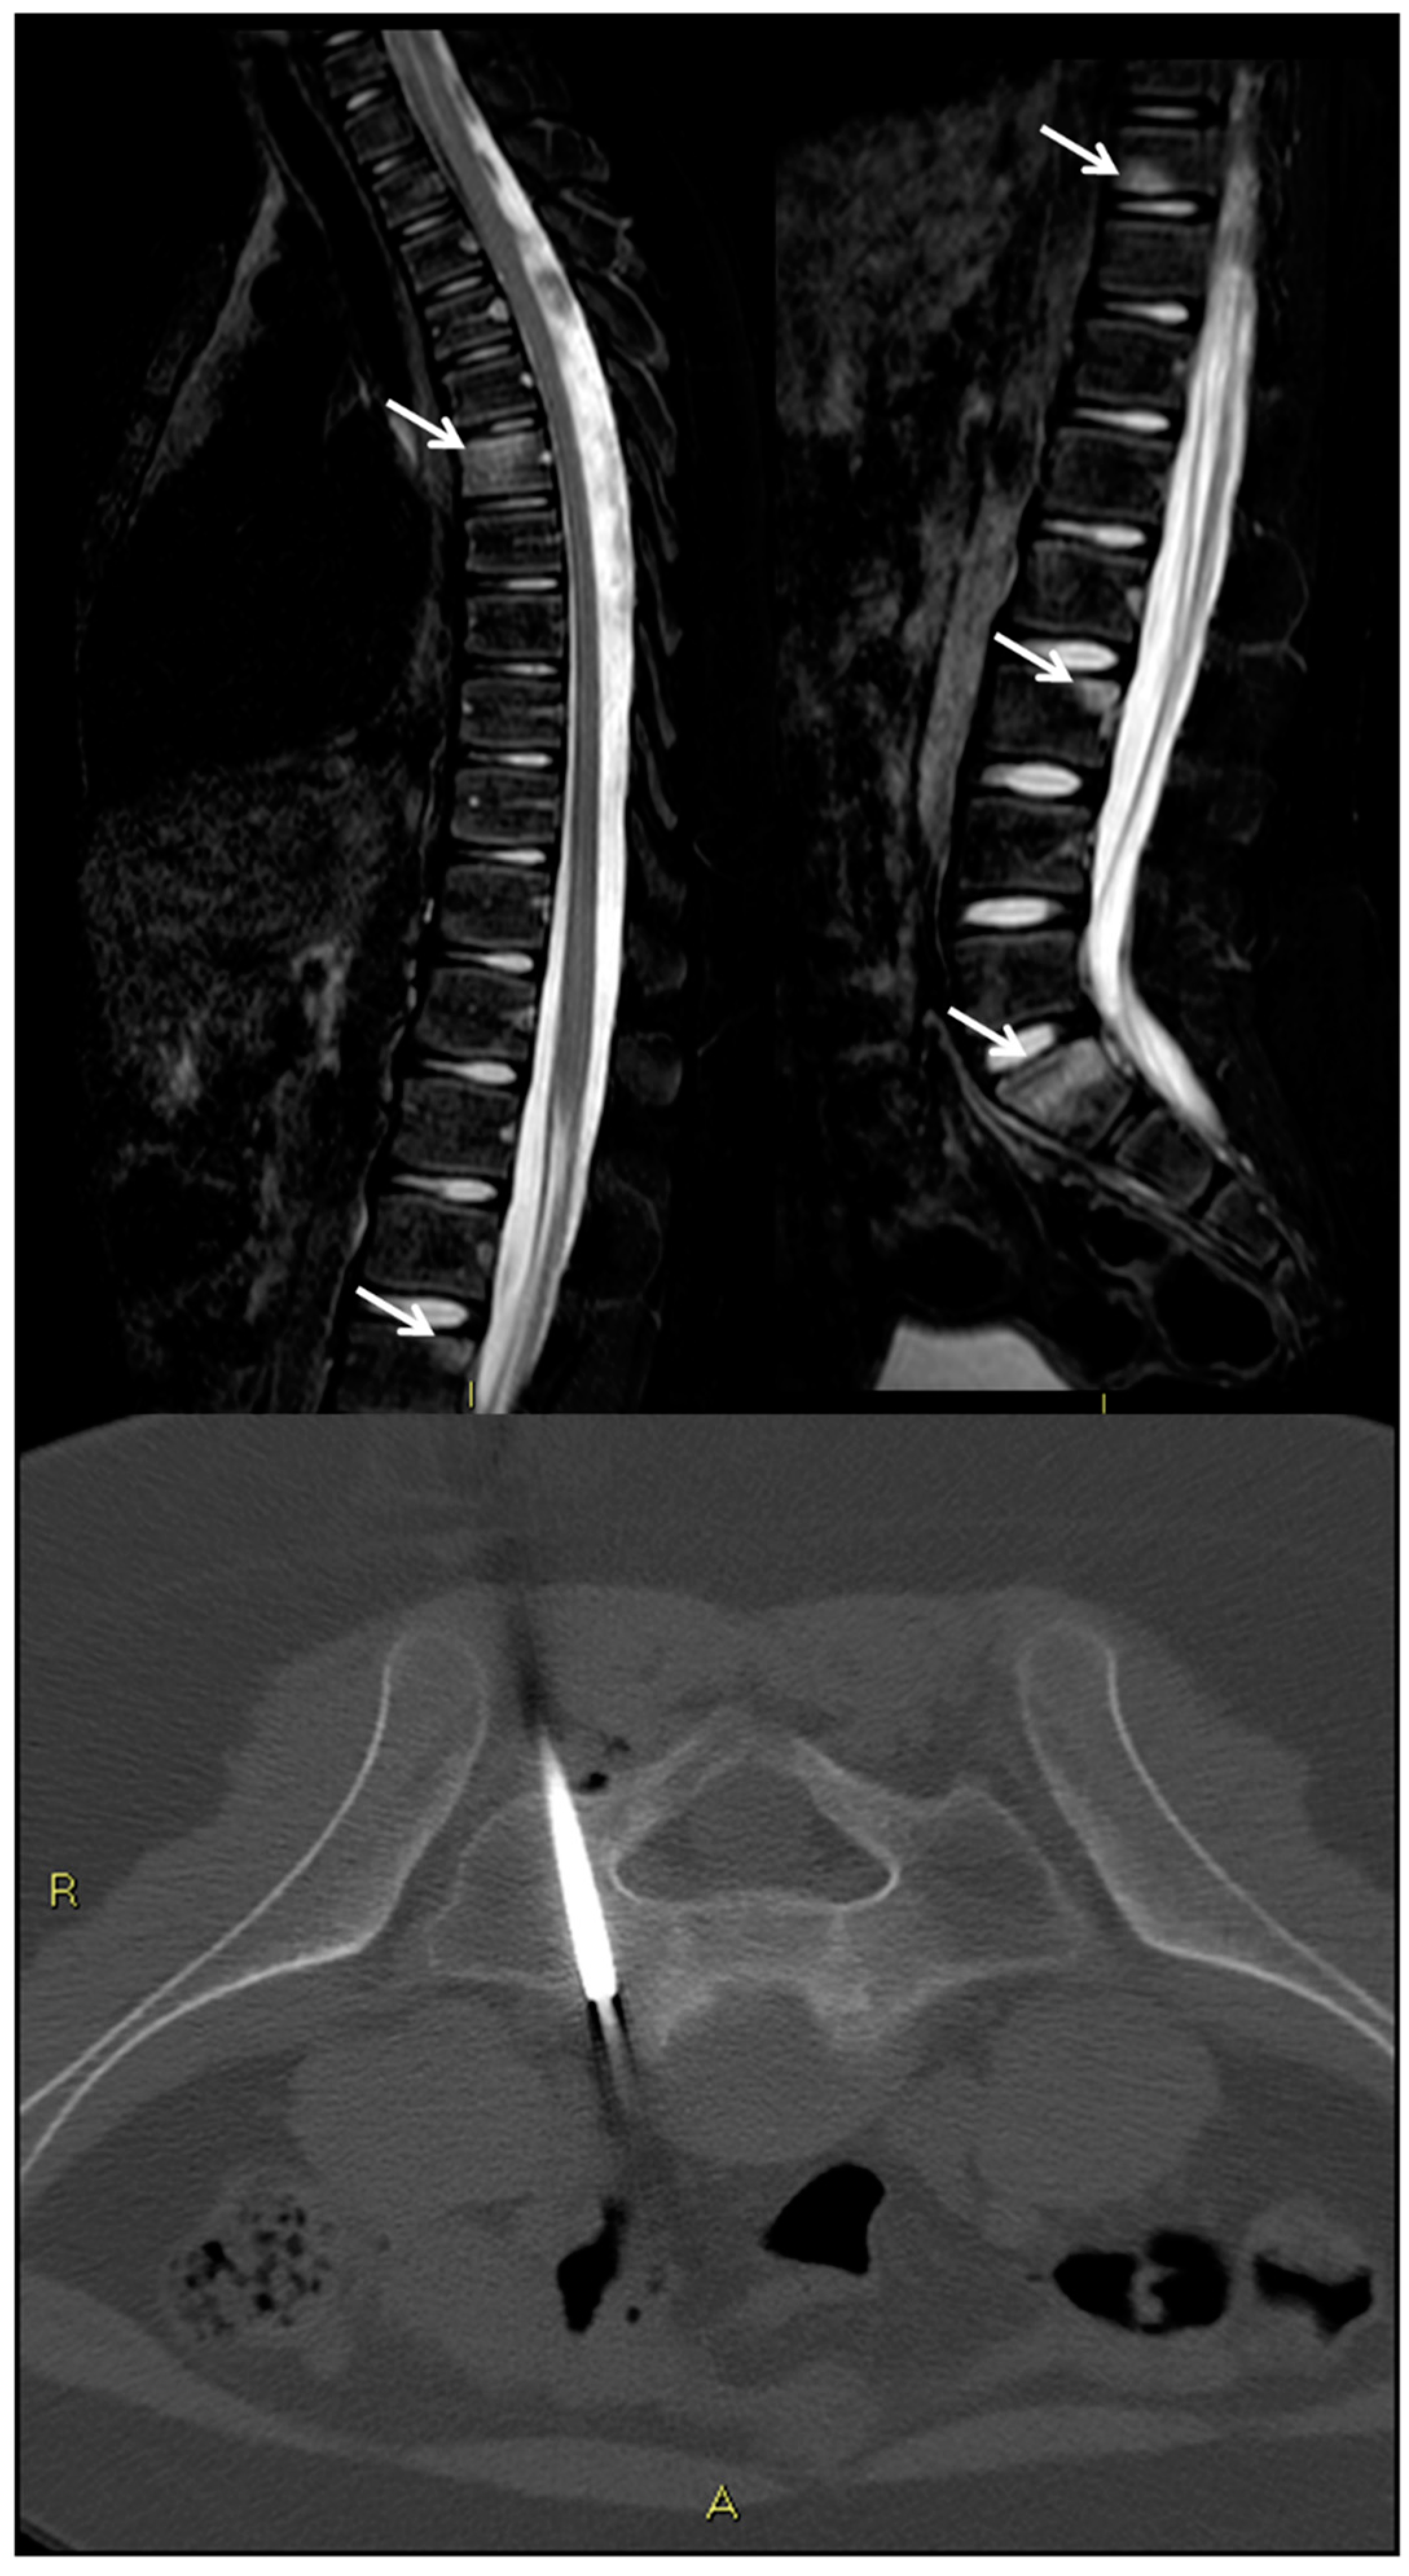

- Michel, S.C.; Pfirrmann, C.W.; Boos, N.; Hodler, J. CT-guided core biopsy of subchondral bone and intervertebral space in suspected spondylodiskitis. AJR Am. J. Roentgenol. 2006, 186, 977–980. [Google Scholar] [CrossRef] [PubMed]

- Dumont, R.A.; Keen, N.N.; Bloomer, C.W.; Schwartz, B.S.; Talbott, J.; Clark, A.J.; Wilson, D.M.; Chin, C.T. Clinical Utility of Diffusion-Weighted Imaging in Spinal Infections. Clin. Neuroradiol. 2019, 29, 515–522. [Google Scholar] [CrossRef] [PubMed]

- Berbari, E.F.; Kanj, S.S.; Kowalski, T.J.; Darouiche, R.O.; Widmer, A.F.; Schmitt, S.K.; Hendershot, E.F.; Holtom, P.D.; Huddleston, P.M.; Petermann, G.W.; et al. 2015 Infectious Diseases Society of America (IDSA) Clinical Practice Guidelines for the Diagnosis and Treatment of Native Vertebral Osteomyelitis in Adults. Clin. Infect. Dis. 2015, 61, e26–e46. [Google Scholar] [CrossRef] [PubMed] [Green Version]

- Naselli, N.; Facchini, G.; Lima, G.M.; Evangelisti, G.; Ponti, F.; Miceli, M.; Spinnato, P. MRI in differential diagnosis between tuberculous and pyogenic spondylodiscitis. Eur. Spine J. 2021. [Google Scholar] [CrossRef]